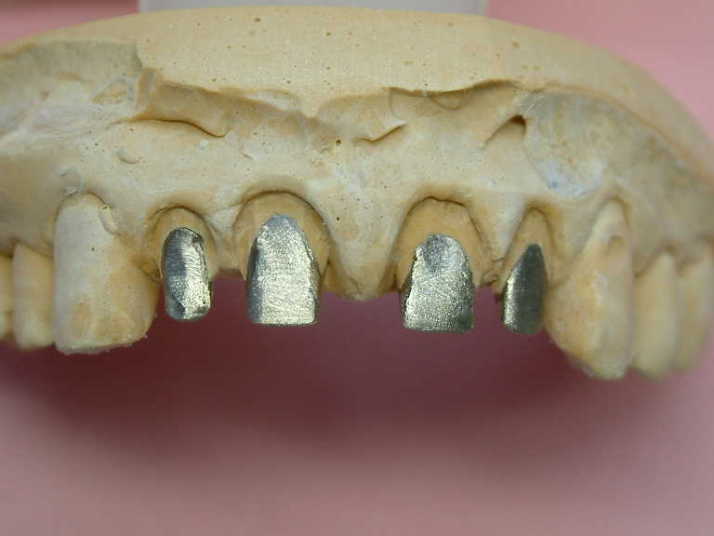

メタルコアー 個歯トレー&各個トレにて印象 |

下顎前歯切端を内側に削って頂いた所 |